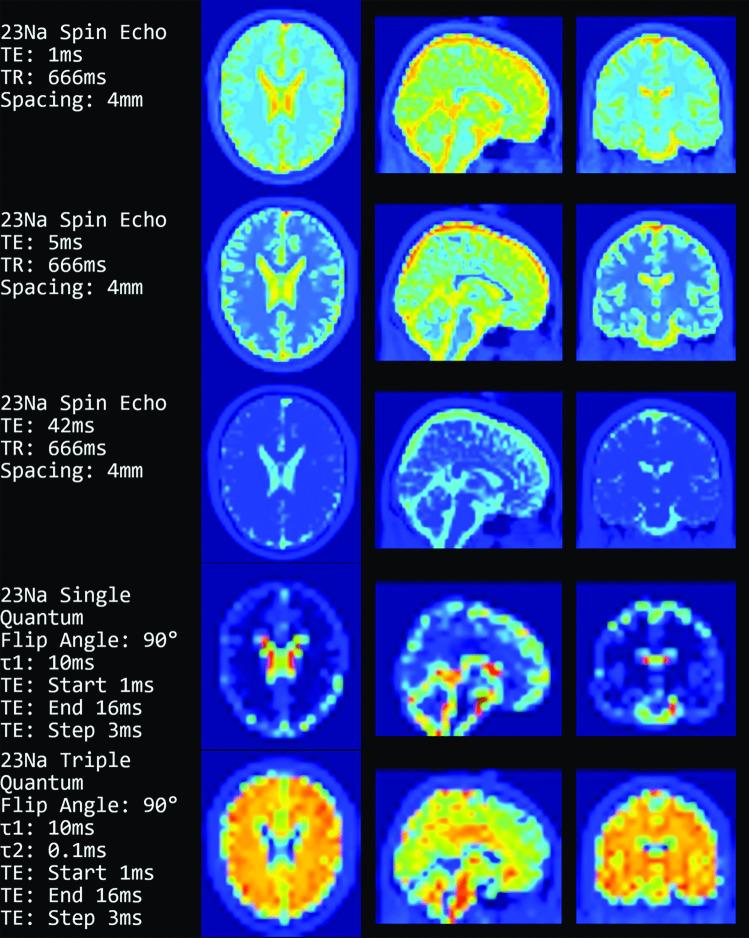

Magnetic resonance image formation is not trivial and remains a difficult subject for teaching. Therefore, we saw an urgent need to facilitate teaching by developing a practical and easily accessible MR image generator. Due to the increasing interest in X-nuclei MRI, sodium image generation is also offered. The tool is implemented as a web application that is compatible with all standard desktop browsers and is open source. The user interface focuses on the parameters needed for the creation and display of the resulting images. Available MR sequences range from the standard Spin Echo and Inversion Recovery over steady-state to conventional sodium and more advanced single and triple quantum sequences. Additionally, the user interface has parameters to alter the resolution, the noise, and the k-space sampling. Our software is free to use and specifically suited for teaching purposes.

磁共振成像是一项不简单的任务,并且仍然是一个难以教授的主题。因此,我们认为有必要通过开发一个实用且易于访问的磁共振图像生成器来促进教学。由于对 X 核 MRI 的兴趣日益增加,我们还提供了钠图像生成功能。该工具作为一个网络应用程序实现,与所有标准桌面浏览器兼容,并且是开源的。用户界面侧重于创建和显示结果图像所需的参数。可用的磁共振序列范围从标准的自旋回波和反转恢复到稳态,再到常规的钠和更先进的单量子和三量子序列。此外,用户界面还有用于改变分辨率、噪声和 k 空间采样的参数。我们的软件是免费使用的,特别适合教学用途。